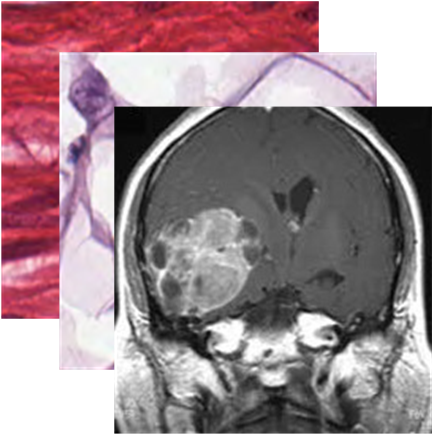

(c) BTMRI

Base Novel HM

CLIP 50.60 51.20 50.89

CoOp 48.93 53.30 51.02

Co-CoOp 52.37 52.80 52.58

MaPLe 53.67 61.60 57.36

Ours 57.00 67.13 61.65

+3.33 +5.53 +4.29

(d) BTMRI dataset

[Uncaptioned image]

Generalization from Base-to-Novel Classes

In our evaluation, we compared the proposed method against several state-of-the-art techniques, including zero-shot CLIP, and prompt learning methods like CoOp, CoCoOp, and MaPLe, thus establishing a robust benchmark for performance assessment. As depicted in Table 7(h), our method outperforms all others in all the medical image recognition datasets. For the base categories, our method demonstrates a remarkable 1.66%percent\% performance improvement. Additionally, when it comes to the novel categories, our method achieves an even more impressive 4.35%percent\% performance improvement. In terms of the harmonic mean, our method elevates the performance from the second-best at 49.45%percent\% to an outstanding 53.08%percent\%. Specifically, our approach excels in the BTMRI dataset, achieving over 3%percent\% performance improvement across all categories. Notably, it achieves a remarkable 5.53%percent\% performance improvement specifically for the novel categories. While our method may not achieve the top performance in terms of novel categories in the CHMNIST dataset, it does obtain the best performance among all prompt-learning methods. Moreover, our method continues to dominate when considering the overall performance evaluation metric, HM. Similar encouraging results are observed in the CCBTM dataset. For the base categories, our method obtains the best performance compared to all prompt-learning methods. Furthermore, the harmonic mean shows a 1.52%percent\% performance gain, further highlighting the strength and effectiveness of our proposed approach.